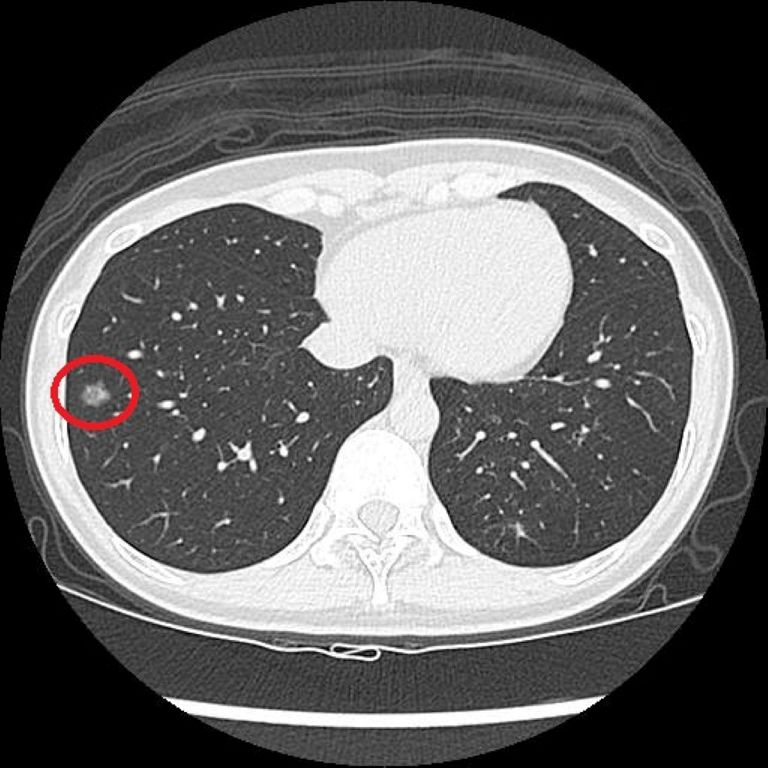

篩檢方面,過去是以胸部X光作為工具,但由於影像為2D平面,對於體積小或位置較隱蔽的病灶辨識能力有限;若是改以一般劑量的電腦斷層檢查,雖能提升解析度,但其輻射劑量相對較高,且需較長時間代謝,不適合作為常規或大規模篩檢工具。而LDCT篩檢則是利用比傳統電腦斷層更低的輻射劑量,從多個角度掃描胸腔,重建出清晰的橫切面和立體影像,有助於偵測肺部的微小結節。洪嘉聰醫師指出,相較於傳統胸部X光只有少數約7%的受檢者會出現疑似異常影像,LDCT能使初次篩檢的陽性比例提升至約23%~24%,大幅增加早期病灶被發現的機會。